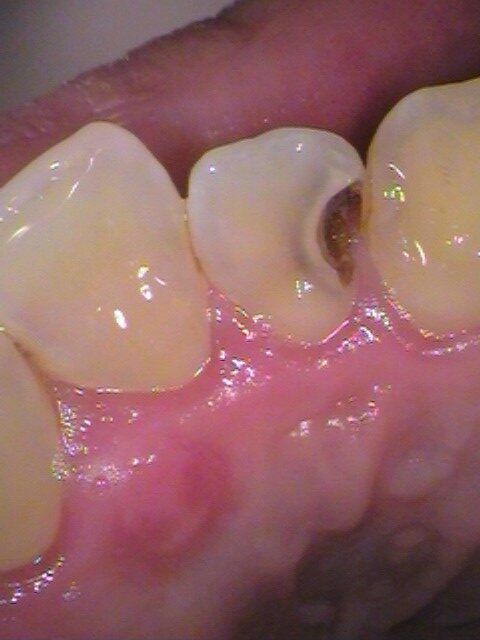

• Before

銀歯の中以外にも、別の箇所からの虫歯。セラミックで治療。